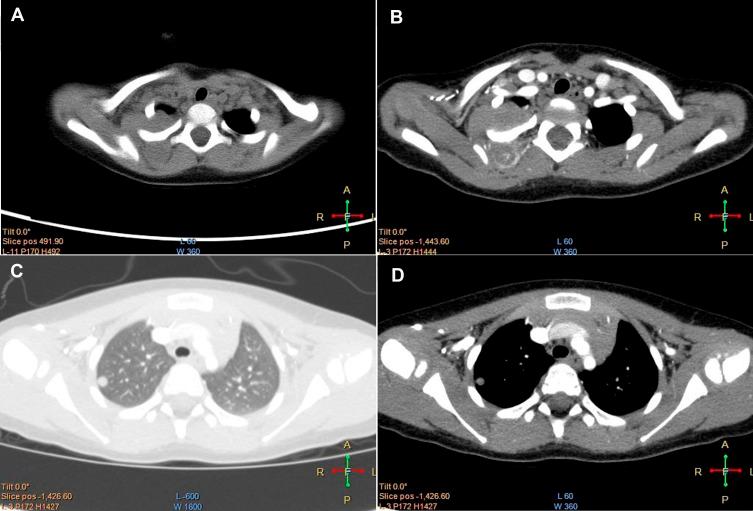

Malignant triton tumor (MTT) is a rare and devastating malignant peripheral nerve-sheath tumor, which shows rapid growth and poor clinical outcomes. Here, we reported a 2-year-old girl who was diagnosed as MTT, an overview of the literature was conducted to discuss the clinical features and optimal treatment strategies of MTT.